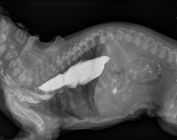

radiographie de gestation chienne

Radiographie de gestation